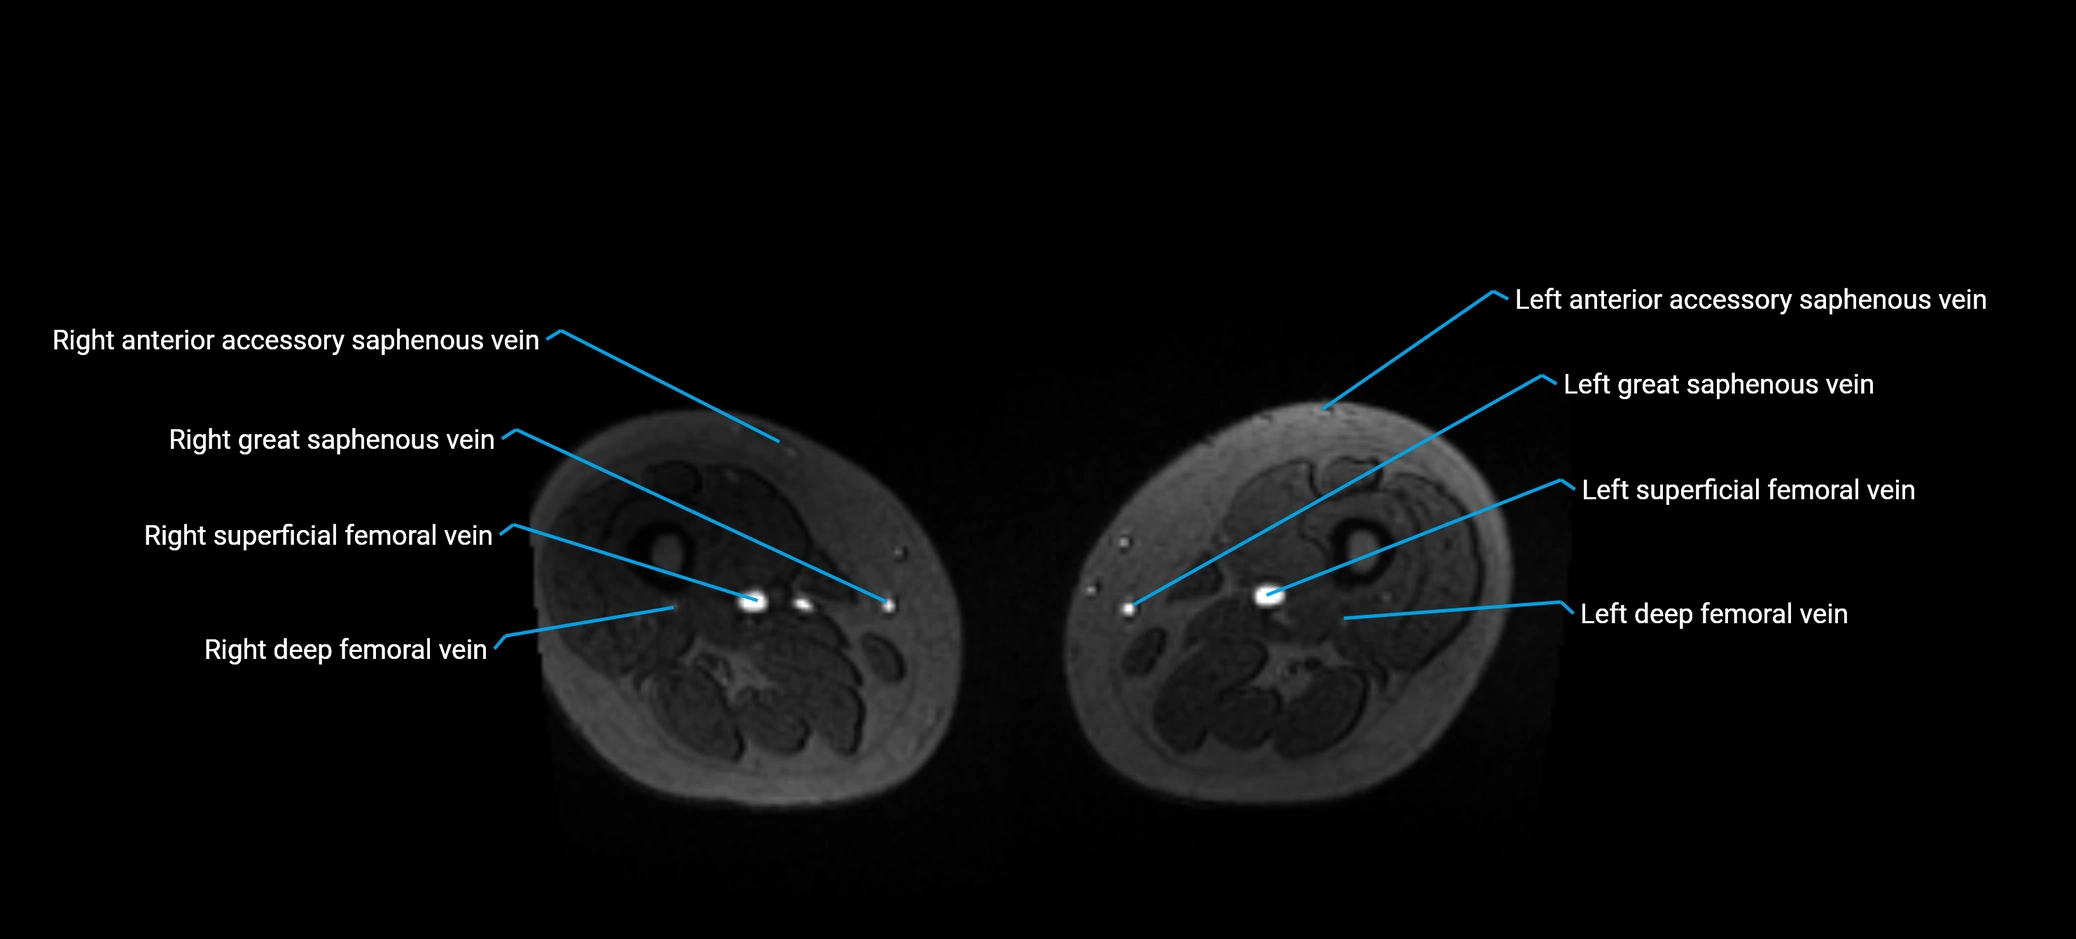

MRI image

image